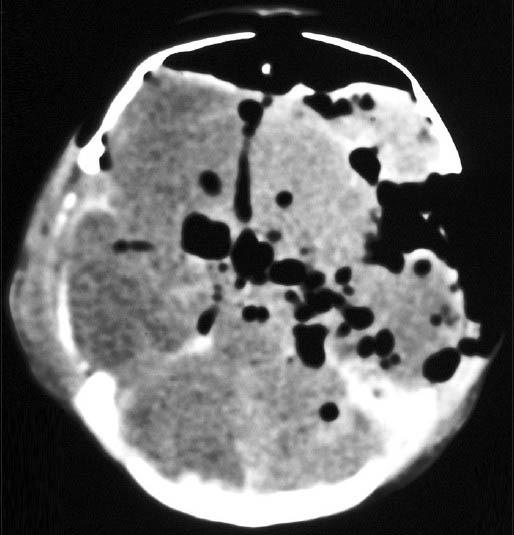

新生儿脑膜炎并发气颅。

Neonatal meningitis complicating with pneumocephalus.

Pneumocephalus is a rare condition characterized by the presence of gas within the cranial cavity. This gas may arise either from a trauma, a tumor, a surgical, or a diagnostic procedure or occasionally from an infection. Pneumocephalus as a complication of bacterial meningitis, in absence of trauma or a procedure, is extremely rare, particularly in a newborn. A case of pneumocephalus occurring in a baby, suffering from neonatal meningitis, acquired probably through unsafe cutting and tying of the cord, is reported here. Cutting, tying, and care of the umbilical cord is of utmost importance to prevent neonatal infection as the same is a potential cause of serious anaerobic infections, besides tetanus.

气颅是一种罕见的病症,其特征为颅腔内存在气体。这种气体可能源于外伤、肿瘤、手术或诊断操作,偶尔也可能源于感染。在没有外伤或操作的情况下,气颅作为细菌性脑膜炎的并发症极为罕见,尤其是在新生儿中。本文报告了一例发生在患有新生儿脑膜炎的婴儿身上的气颅病例,可能是通过不安全的脐带剪断和结扎感染的。脐带的剪断、结扎和护理对于预防新生儿感染至关重要,因为除了破伤风外,这也是严重厌氧菌感染的潜在原因。